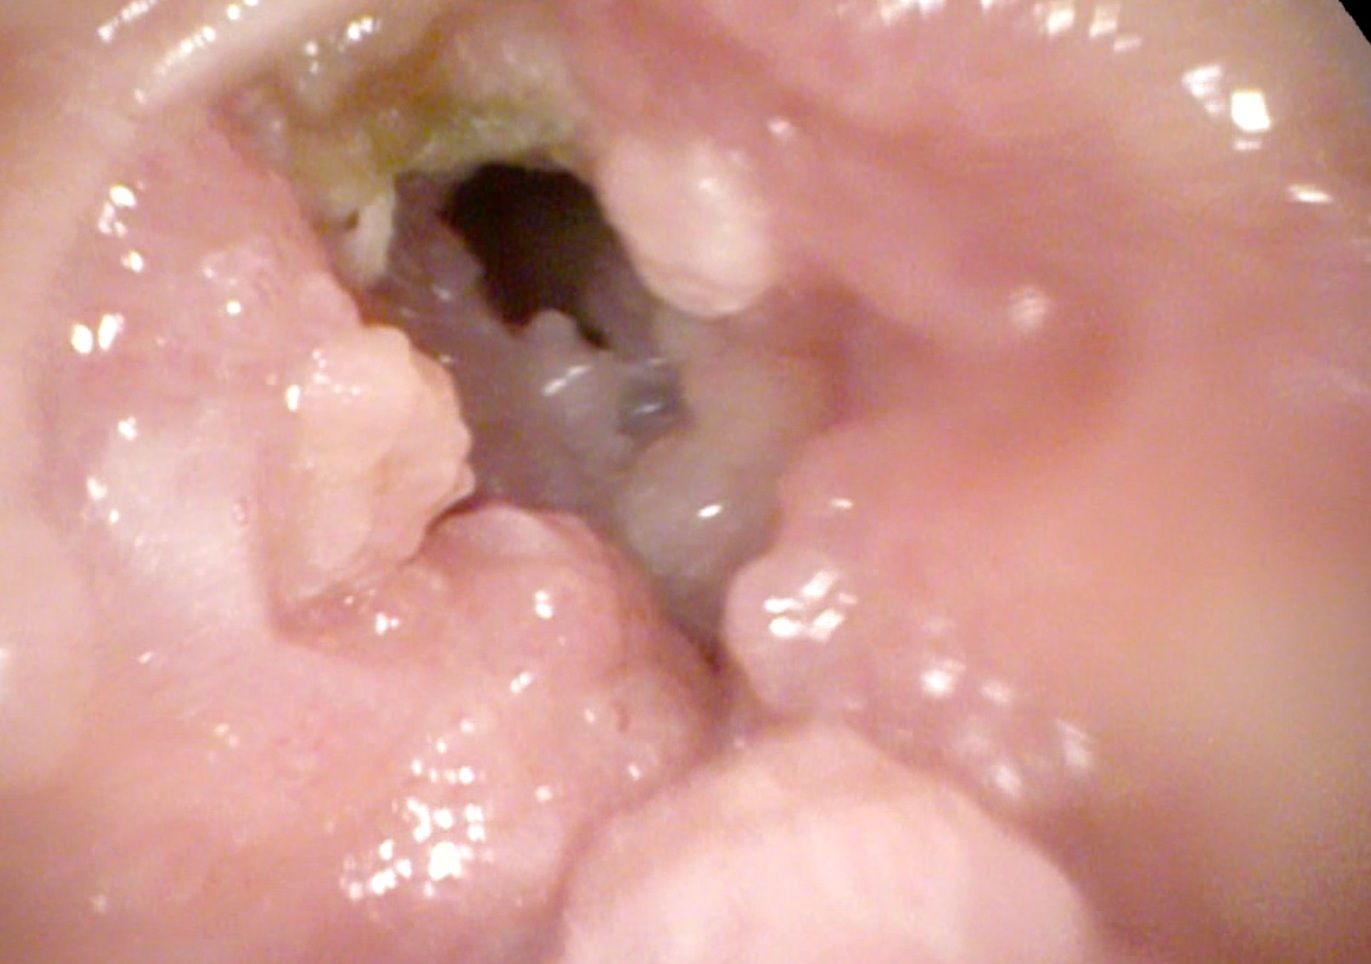

- Дуктография молочных желез – рентгенография каналов с добавлением контрастного вещества. Помогает изучить образование в молочных железах изнутри, участки повреждения, расположение относительно других тканей, возможную онкогенность. Особенность процедуры заключается в вводе контраста в главный проток, открывающийся в соске. На фото выше показан результат дуктографии.

Последнее обследование проводят с помощью введения контрастного вещества, которое покажет локализацию папиллом в протоках. Однако пациенткам не обязательно проходить все виды инструментальной диагностики, иногда бывает достаточно одного УЗИ.

Дуктография представляет собой рентген с введением контрастного вещества в главный проток — через сосок. Этот метод позволяет выявить не только локализацию и форму бородавок в протоках, но и определить вероятную онкогенность. Дуктография невозможна при наличии атипических клеток.